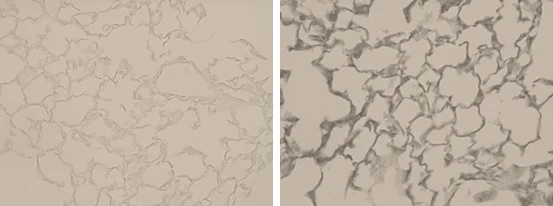

Immunohistochemistry (Formalin/PFA-fixed paraffin-embedded sections) - Anti-Elastin antibody (AB21610)

Immunohistochemical analysis of Bouin's solution fixed (25cm H2O pressure for 90 min) paraffin-embedded wild type mouse lung (12mo, female) tissue labeling Elastin with ab21610 at 1/50 dilution, followed by HRP-conjugated secondary antibody.

Left Panel : No antibody control.